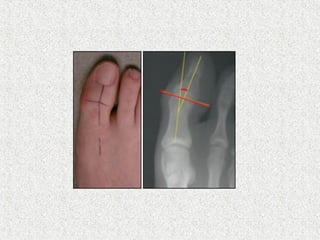

o Valgus deformity

o Aesthetic or cosmetic concerns

 Standard radiograph

 Weight bearing

AP

Lateral

 Non standing

Oblique

Axial sesamoid view